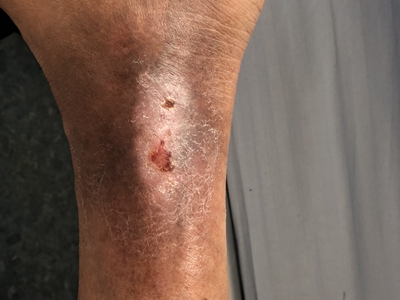

膝盖

结痂 · 斑

臁疮膝盖上有褐色结痂斑块图

膝盖出现臁疮皮损时,会见到呈指甲大小的圆形、不规则形斑片,呈红色,上有暗褐色结痂形成,表面干硬,有白色脱屑形成,大腿及小腿部位皮肤也有皮损波及。